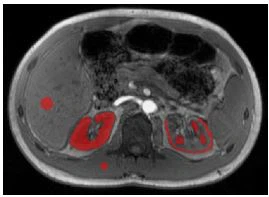

Ohjelmistoa ITK-SNAP (versio 3.8.0, University of Pennsylvania) käytettiin kiinnostavien alueiden (ROI) piirtämiseen manuaalisesti paravertebraaliseen lihaskudokseen (336 pikseliä), maksassa (900 pikseliä), koko alueelle.munuainen(5533±1792 pikseliä ja 4756±1142 pikseliä vasemmalle ja oikeallemunuaisetvastaavasti),munuaistencortex (1260±279 pikseliä ja 1245±265 pikseliä vasemmalle ja oikealle munuaiselle, vastaavasti) ja munuaisydin (993±293 pikseliä ja 962±392 pikseliä vasemmalle ja oikealle munuaiselle, vastaavasti) (kuva 3). Kaikki ROI:t piirrettiin kolmelle peräkkäiselle viipaleelle ja keskimääräinen herkkyys ja keskihajonta (SD) laskettiin kullekin elimelle ja kohteelle. Paravertebraalista lihaskudosta käytettiin QSM:n kvantifioinnin referenssinä nykyisessä tutkimuksessa herkkyysarvojen johdonmukaisuuden varmistamiseksi (lisämateriaali, taulukko S1) [27].

Kuva 3 Esimerkki ROI-sijoituksesta. Vatsan suuruuskuva, jossa on esimerkillisiä kiinnostavia alueita (ROI) piirrettynä paravertebraaliseen lihaskudokseen (336 pikseliä), maksaan (900 pikseliä), koko munuaiseen (5533±1792 pikseliä ja 4756±1142 pikseliä vasemmalle ja oikealle munuaiselle). ),munuaistencortex (1260±279 pikseliä ja 1245±265 pikseliä vasemmalle ja oikeallemunuaiset) ja munuaisydin (993 ± 293 pikseliä ja 962 ± 392 pikseliä vasemmalle ja oikealle munuaiselle, vastaavasti)